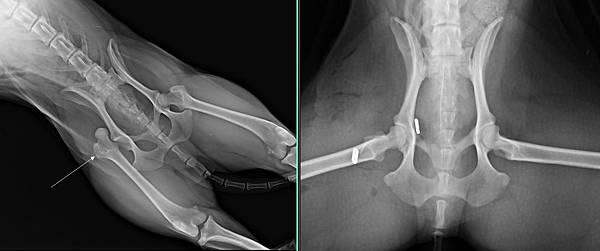

右腳髖關節脫臼兩周了

手術前

手術安裝髖關節人工韌帶後

手術後兩周

很快恢復走跳的能力